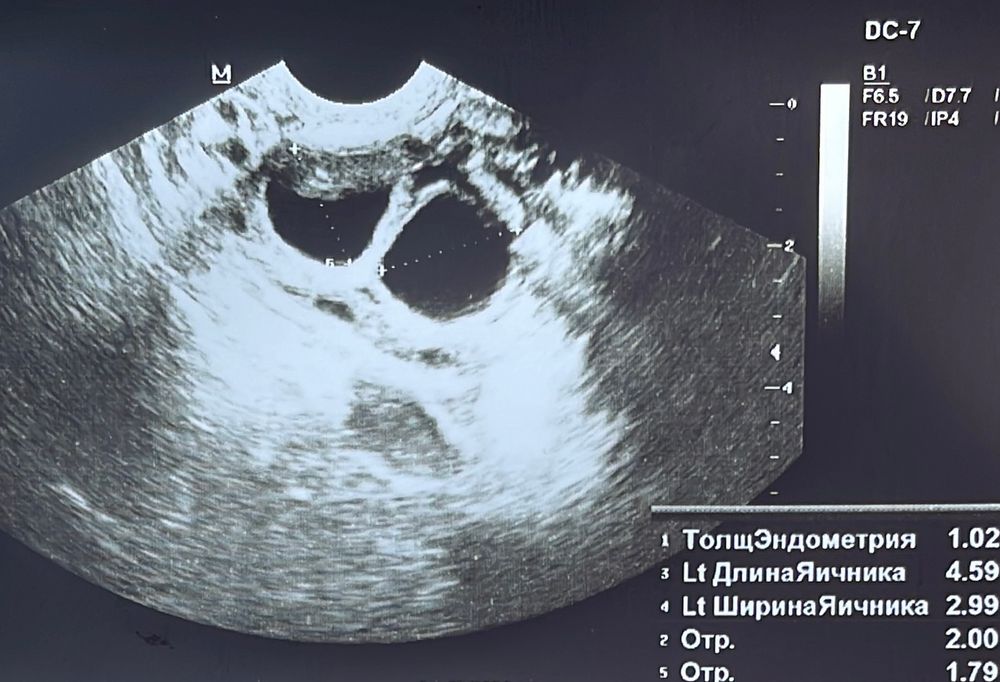

Помогите с узи

3 стимуляции летрозола-мимо. Следующий этап-каутеризация яичников Инсеминация. 10 дпу Овитрель 6500МЕ